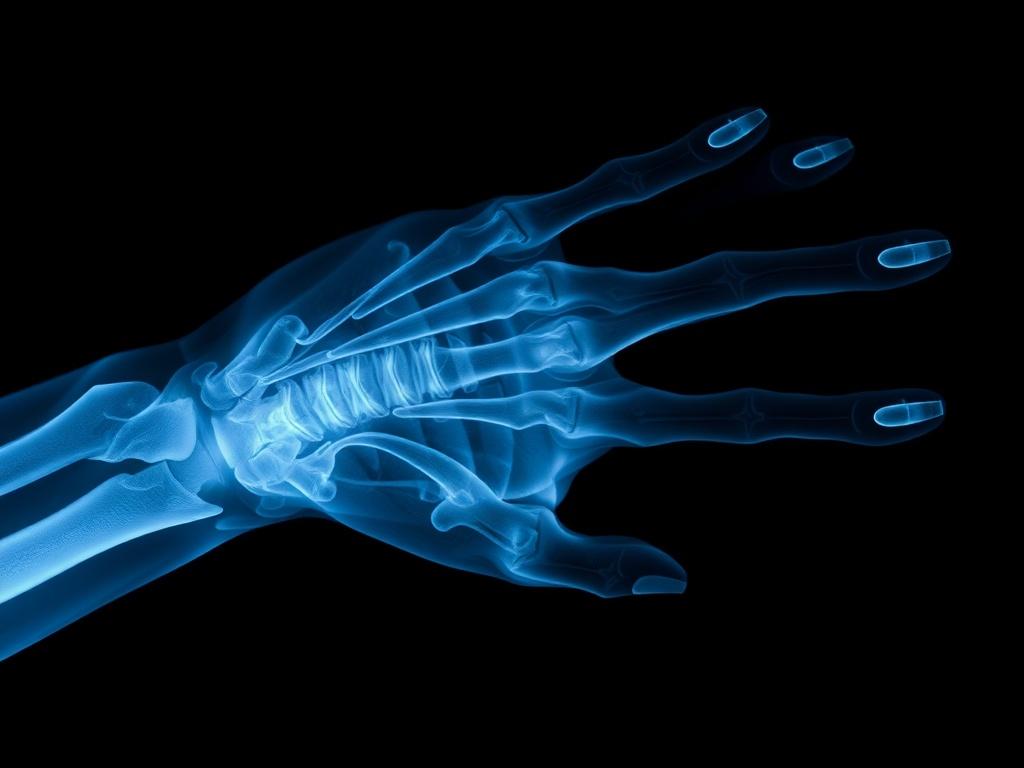

Рентгеновские лучи — это разновидность электромагнитного излучения, похожего на свет, но с гораздо большей энергией. Они проходят сквозь ткани по-разному: кости задерживают их сильнее, мягкие ткани — слабее, а воздух почти не мешает. На основании этой разницы получается изображение с контрастом.

В рентгеновской трубке электроны, ускоренные электрическим полем, ударяют по мишени и вызывают кратковременное излучение рентгеновских фотонов. Эти фотоны либо проходят через тело к детектору, либо взаимодействуют с атомами тканей и теряют энергию. Детектор фиксирует распределение прошедших фотонов, и компьютер преобразует это в снимок, который врач оценивает.

Рентгенография — это классический снимок плоской проекции. Его делают, когда нужно быстро увидеть форму и положение костей, оценить состояние легких или определить инородные тела. Снимки прозрачны и понятны: светлые участки соответствуют плотным структурам, темные — воздухосодержащим.